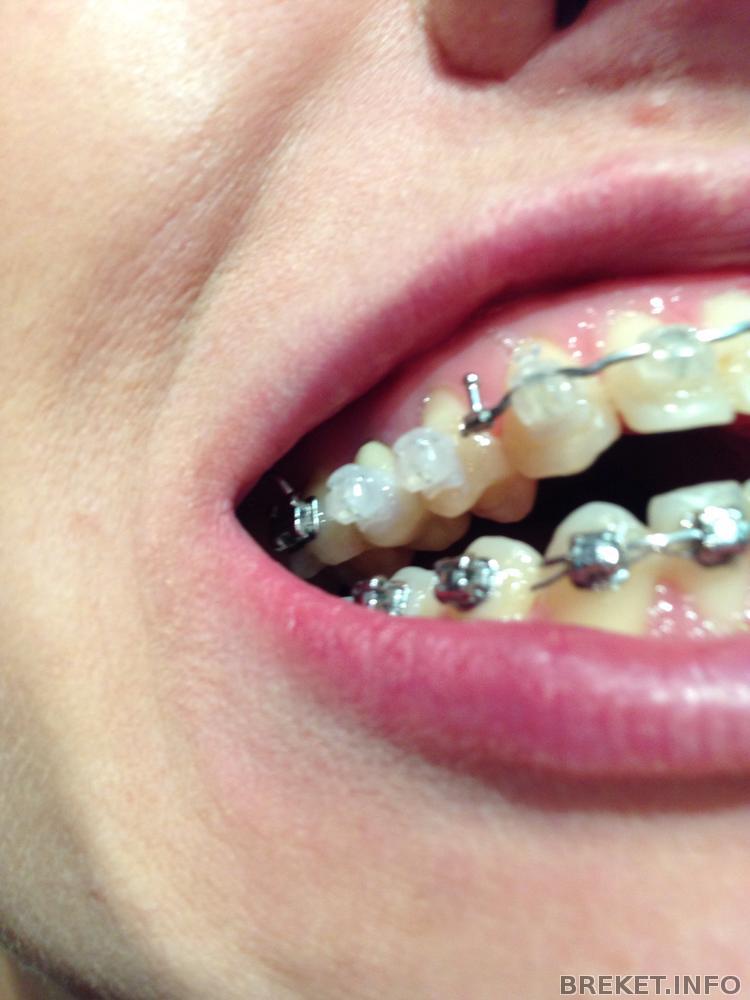

У орта я была 15 мин) за это время меня заменили сломанный брекет на 4, заменили 2 дуги и поставили брекеты на НЧ на 7)

Когда заменили брекет, думала, что зуб выдирают.. Ощущения не из приятных...

Зубки уже сутки офигевают... Боль адская после смены дуг.. Кушать не могу, зубки "чешутся"...

Надеюсь через пару дней все пройдет))